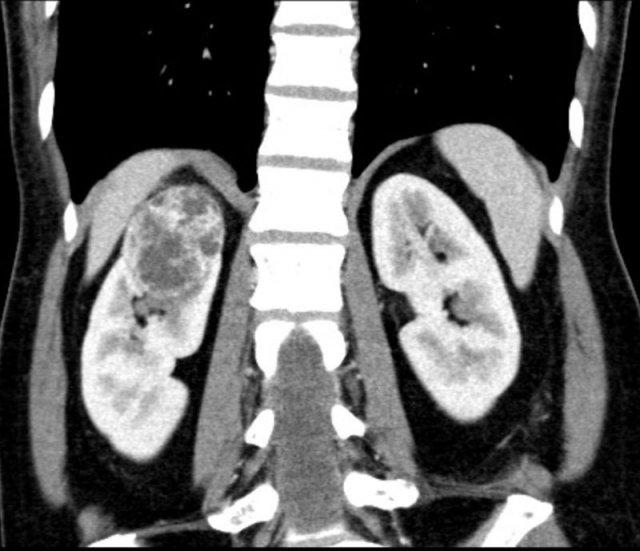

Ca lâm sàng 1

CT của một tổn thương đặc với các thành phần dạng nang/hoại tử nhỏ hơn.

Vì hơn 25% khối lượng được cấu thành bởi mô đặc, đây có khả năng là khối hoại tử thay vì tổn thương dạng nang.

Không nên sử dụng tiêu chí Bosniak.